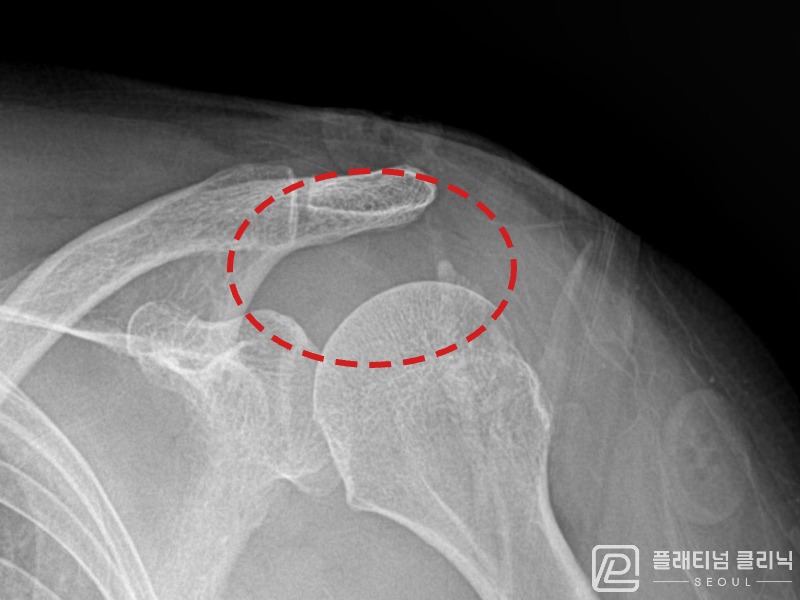

[촬영시기:21.11.04~21.11.09]

[석회분쇄흡입술] 우측 어깨 극심한 야간 통증으로 수면이 불가능해진 50대 여성 환자로, X-ray에서 우측 극상근건 내 석회 침착이 확인되어 석회분쇄흡입술을 시행하였습니다.